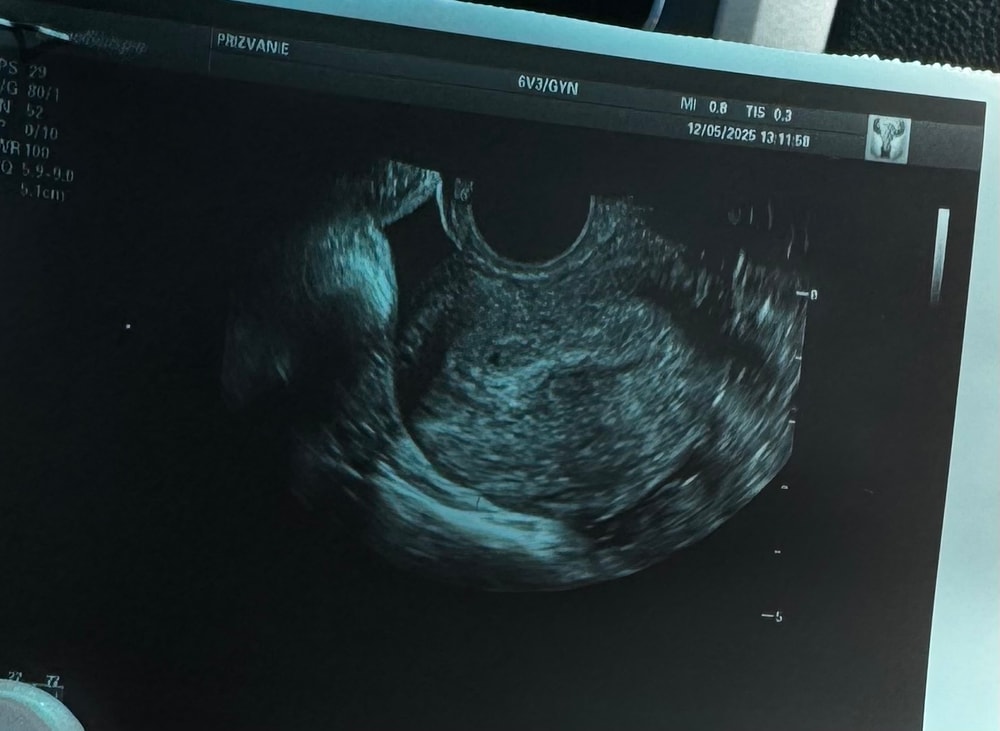

Если плодное яйцо неправильной формы , значит есть тонус матки 🤔🤔🤔

Арина, мне моя Ре говорит - генетические отклонения эмбриона зачастую влияют на форму ПЯ.

Так вы до пикселей увеличили, естественно оно не будет выглядеть круглым.

Галка, вот и меня это смутило, но узистка заверила, что 100% беременность малого срока. Тесты с хорошей полосой, хгч сдала, жду

Алиса , может из за того что увеличили так сильно

Короче пока вообще сложно сказать и не сильно информативно. Дождитесь хгч и через неделю повторите узи